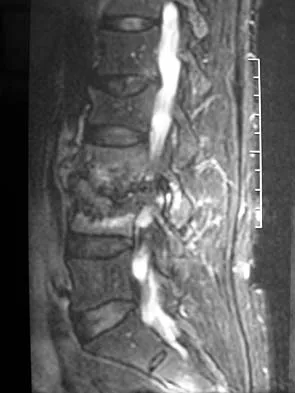

Figures 1a and 1b show the sagittal T2- and T1-weighted MRI scans of a 25-year-old intravenous drug abuser who has low back pain that is increasing in intensity. Laboratory studies show a WBC count of 10,000/mm3 and an erythrocyte sedimentation rate of 80 mm/h. Blood culture is negative. Initial management consist of